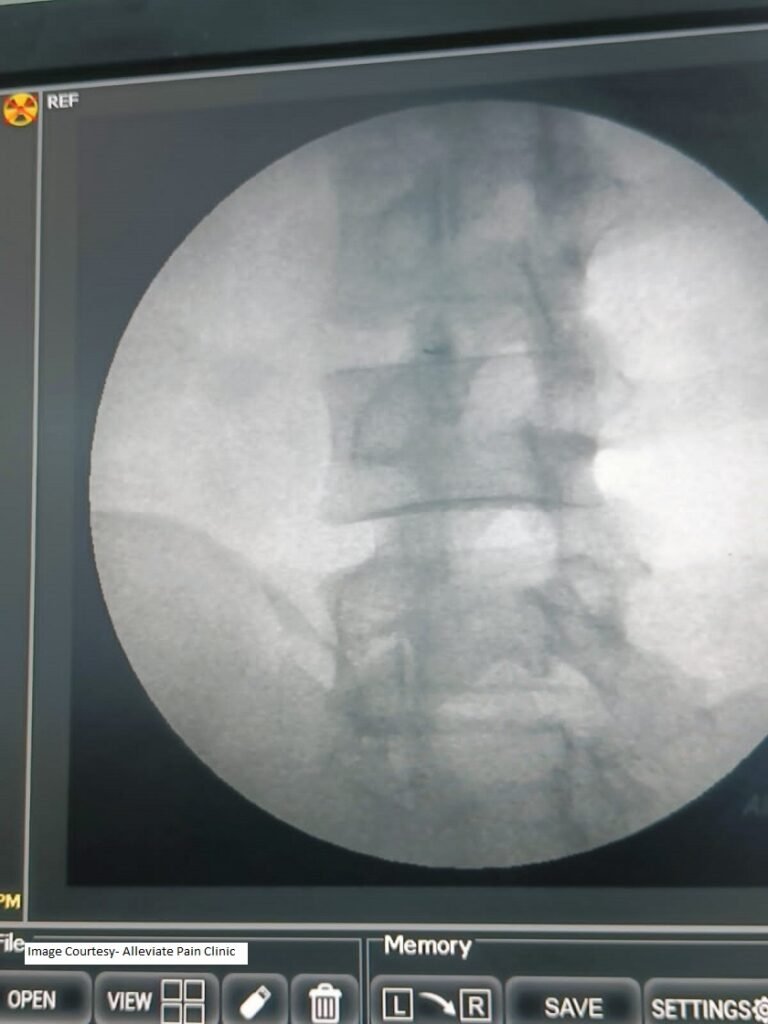

Intra-articular facet joint injections involve the direct injection of medication, such as corticosteroids, into the facet joint space. These injections can reduce inflammation and provide pain relief. Imaging guidance ensures precise placement of the needle into the joint, increasing the effectiveness of the treatment.

- Image taken from- Inklebarger J. Long-term follow up Results of Ongley method Prolotherapy Combining Lumbar Manipulation, targeted Spinal Injections, and Mckenzie-type Rehabilitation Exercises for the Management of Arthropathic low back pain: A Case Report with 9-year follow up. Ortho & Rheum Open Access 2017; 9(3): 555763. DOI: 10.19080/OROAJ.2017.09.555763